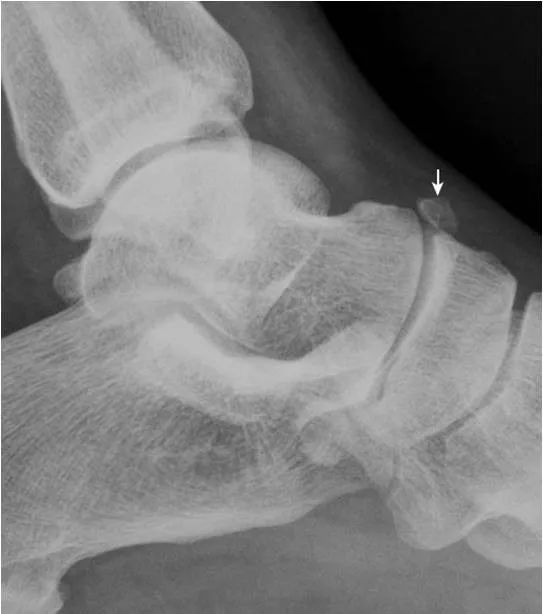

1.跟骨结节骨骺:

形态多样,密度致密(箭),伴裂隙(箭头),为正常表现,勿误认为坏死。

2.Haglund外生骨疣与不典型骨刺:

跟骨后上缘骨刺样突起(箭),属正常变异,称Haglund外生骨疣。穿高跟鞋时可损伤相邻的跟腱,形成Haglund综合征;跟骨结节下缘前突骨刺样突起(箭头),正常人可见,可无临床症状。